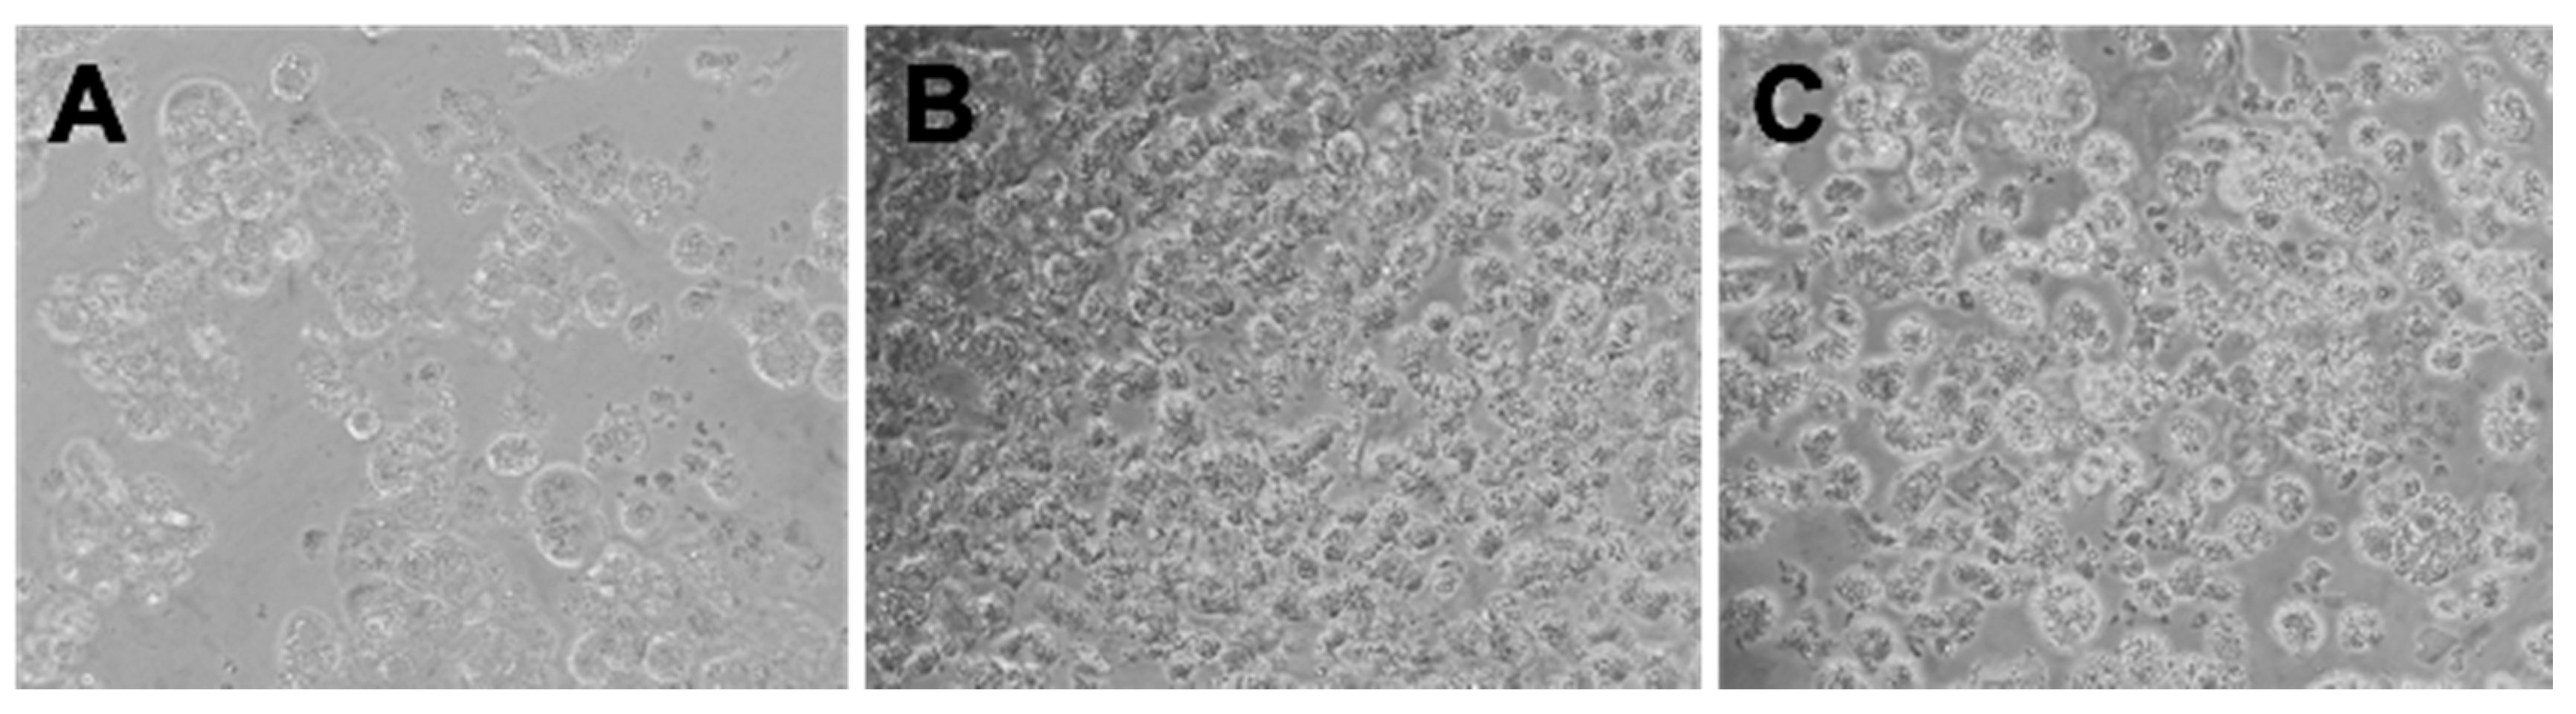

3.2. Coffee Pulp Is Not Toxic and Regulates ROS Production and the Accumulation of Lipids in Hepatocytes